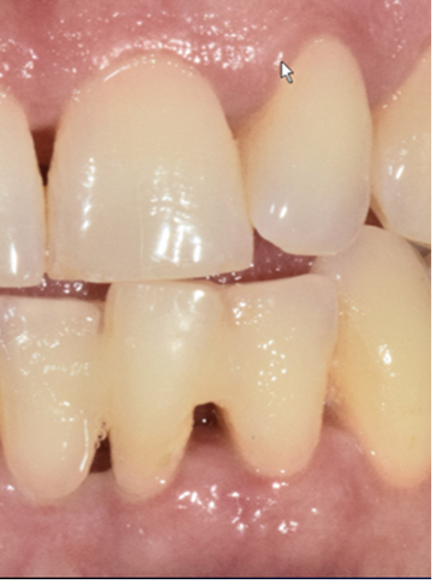

She was hitting tooth #24 every time she closed her mouth—and it hurt badly. The gingival tissue was visibly swollen, and the tooth had Class III mobility.

- Occlusal adjustment—we reduced the incisal edge so she stopped traumatizing the tooth.

My son, Dr. Matt Sheldon, splinted tooth #24 (to #23 and #25), but she was feeling better even before the splint was placed. Infection control—not extraction—was already changing the outcome.

Look at tooth #24. Bone regenerated.